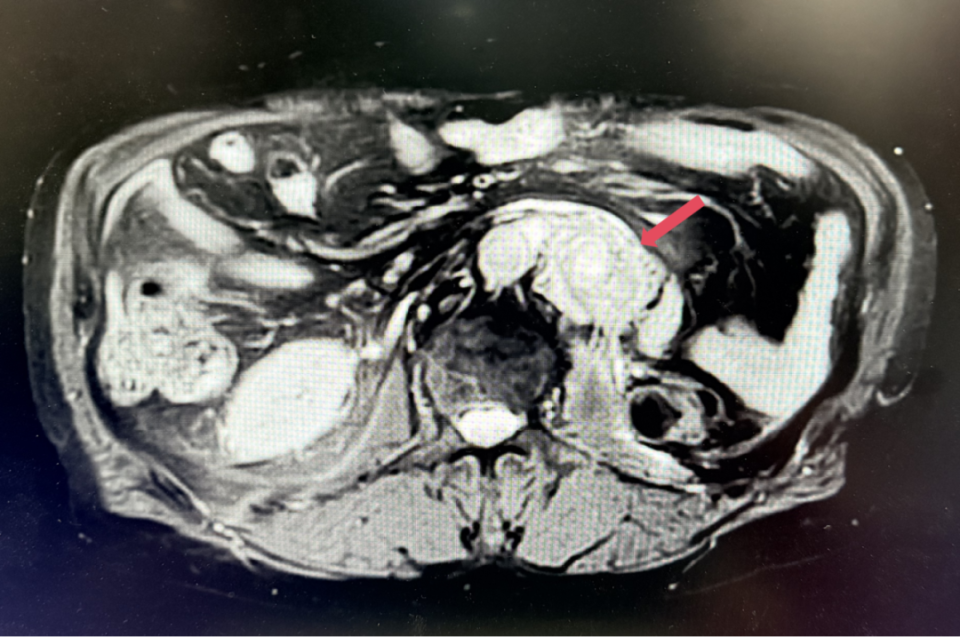

2023年3月,初始应答